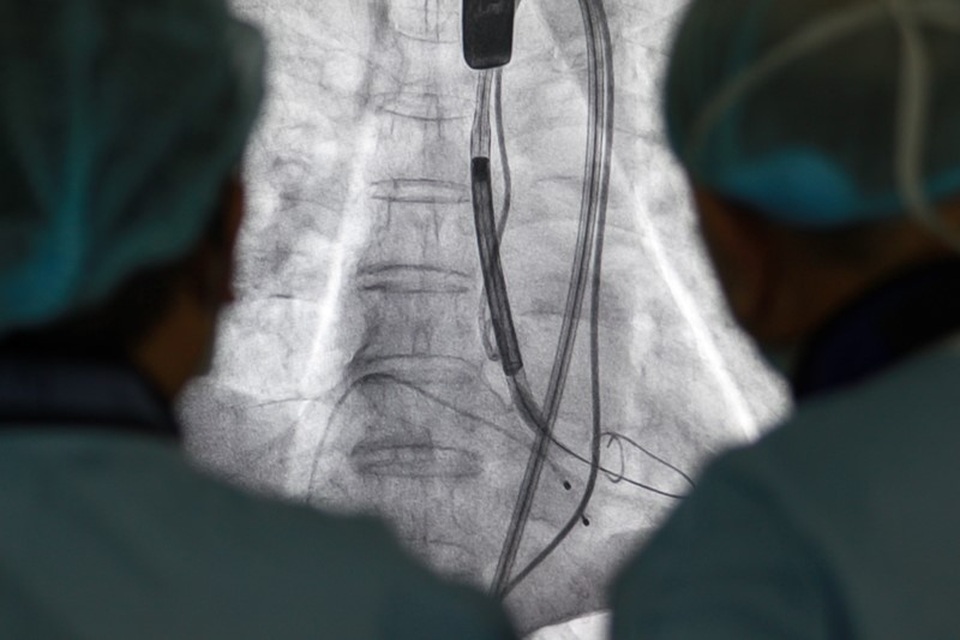

Ống thông được luồn qua da từ động mạch đùi đến động mạch chủ để thay van tim cho bệnh nhân

Giải pháp tối ưu với ông C. là thay van động mạch chủ qua da (TAVI). Đây là một trong những kỹ thuật thay van tim hiện đại và phức tạp nhất thế giới. Với kỹ thuật này, các bác sỹ sẽ luồn ống thông qua da từ động mạch đùi đến động mạch chủ để thay van tim, giúp tăng khả năng thành công, giảm nguy cơ chảy máu, tránh được nhiều biến chứng nguy hiểm. Thời gian phục hồi của người bệnh cũng nhanh hơn - chỉ từ 2 đến 6 ngày so với 1 - 2 tuần nếu mổ mở.